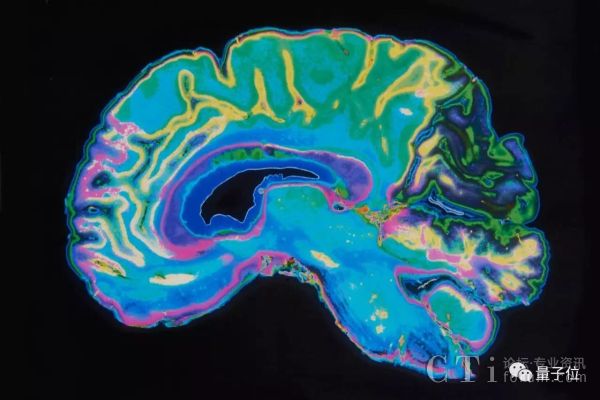

最近,IBM和阿尔伯塔大学联手进行了一项开创性的研究,使用简单的MRI(磁共振成像)扫描加一个神经网络,就能通过大脑的血流情况,来诊断神经分裂是否会发病,以及症状的严重程度。

这个研究团队,首先使用95份匿名fMRI(功能性磁共振成像)图片训练神经网络,这个数据集包括精神分裂患者和健康对照组。这些图片反映的是完成简单的音频联系后,脑内血液流动的情况。最后这个网络分辨患者和对照组的准确率达到74%。